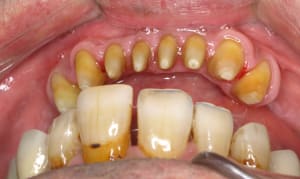

Implant 34 ETK 3,5 12mm.jpg